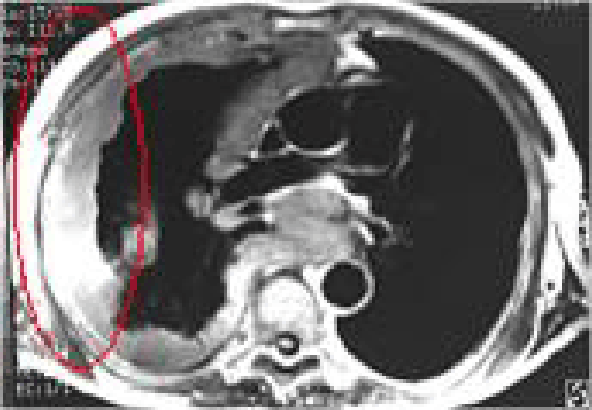

미만성 흉막비후(잠복기 약 15~20년)

잠복기가 약 15~20년에 걸친 석면으로 인한 미만성 흉막비후에 대한 CT사진

폐를 둘러싸는 흉막이 석면에 의해 전체적으로 비대(미만성)해 지면서 폐의 팽창을 방해해 호흡이 곤란해지는 질병 폐기능 장해단계가 고도장해인 경우